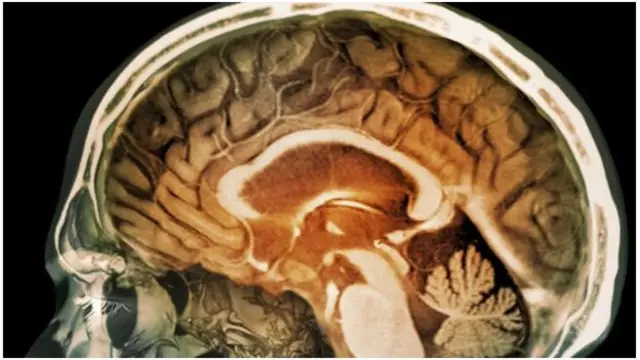

شیفیلڈ یونیورسٹی کے پروفیسر ایلن پیکی کا کہنا ہے کہ ’تعجب کی بات تو یہ ہے کہ مرد پرکشش نظر آنے کے غرض سے جِم جاتا ہے، تاکہ خواتین اس کی طرف متوجہ ہوں۔ لیکن یہ سب کرنے سے ان کی بچے پیدا کرنے کی صلاحیت کم ہوتی ہے۔‘اینابولک سٹیرائڈز دماغ کے پیچوٹری غدود پر اثرانداز ہوتے ہیں، جس سے لگتا ہے کہ خصیوں کی کارکردگی بہت بڑھ گئی ہے۔

ایسے میں یہ غدود ایف ایس ایچ اور ایل ایچ ہارمونز بنانا چھوڑ دیتا ہے اور سپرم کی افزائش کے لیے یہ ہارمونز نہایت کلیدی حیثیت رکھتے ہیں۔